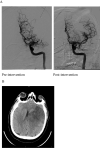

Background and purpose: Coronavirus disease 2019 (COVID-19) is a global pandemic that causes flu-like symptoms. There is a growing body of evidence suggesting that both the central and peripheral nervous systems can be affected by SARS-CoV-2, including stroke. We present three cases of arterial ischemic strokes and one venous infarction from a cerebral venous sinus thrombosis in the setting of COVID-19 infection who otherwise had low risk factors for stroke.

Results: There were 3 cases of arterial ischemic strokes and 1 case of venous stroke: 3 males and 1 female. The mean age was 55 (48-70) years. All arterial strokes presented with large vessel occlusions and had mechanical thrombectomy performed. Two cases presented with stroke despite being on full anticoagulation.

Conclusions: It is important to recognize the neurological manifestations of COVID-19, especially ischemic stroke, either arterial or venous in nature. Hypercoagulability and the cytokine surge are perhaps the cause of ischemic stroke in these patients. Further studies are needed to understand the role of anticoagulation in these patients.